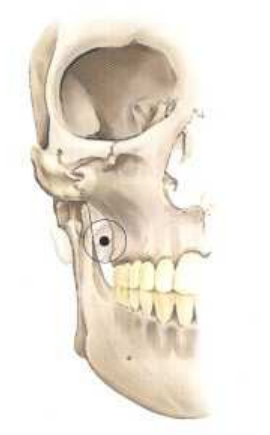

5.下圖中的麻醉注射方式,為下列那一種?

(A)Vazirani-Akinosi mandibular block (B)Gow-Gates mandibular block (C)Posterior superior alveolar nerve block (D)Mental nerve block